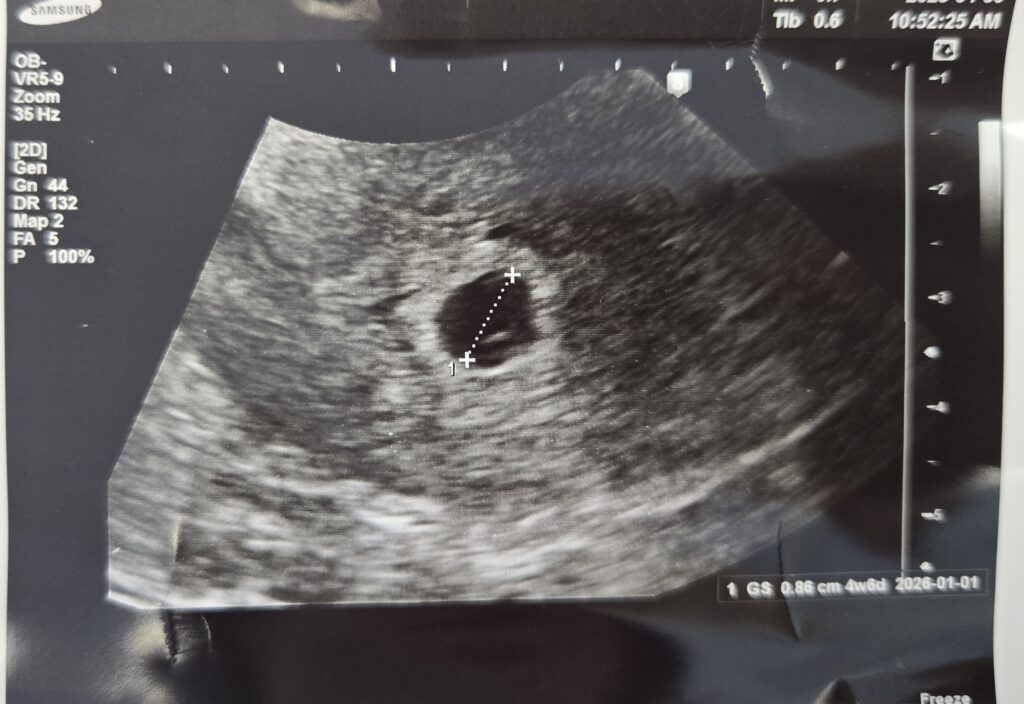

그리고 드디어 만난 아기집 !

그동안 산부인과 정기검진 때는 아무것도 없던 초음파에 동그랗게 아기집이 생겨있었다.

다행히 잘 있는 아기, 이제 난황도 보였다.

난황 끝에 아기가 있다고 하던데 아기까지는 잘 안보였지만 5주차에 난황을 보게 돼서 한시름 놓을 수 있었다.

아기집이 0.86 센치라니,, 지금와서 보니 엄청 작고 소중하다 !